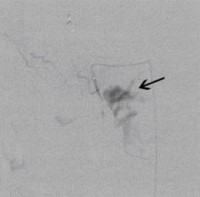

Postoperative abdominelle Blutungen bei chronischer Pankreatitis (Pfeile: Art. hepatica und Art. gastroduodenalis).

(Bild 1 von 5)